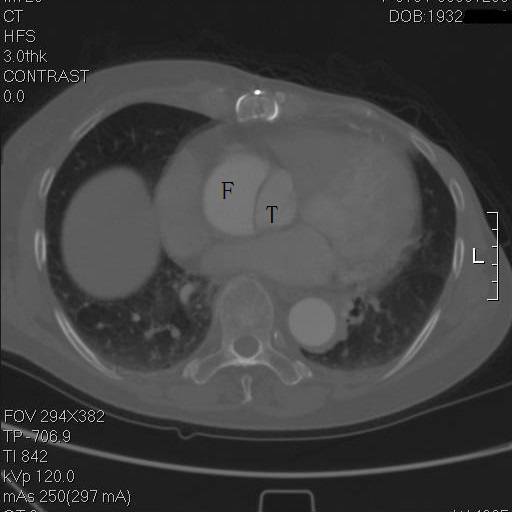

患者是一例A型主动脉夹层,上图中F示假腔,T示真腔,这没什么奇怪。但仔细一看,胸骨的边缘具有高密度影,中间还有一小片低密度区,这例病例接受过前胸正中开胸的手术。

是的,回忆其病史,她一年半前,罹患A型主动脉夹层,第一内膜破裂口在右冠上方,夹层延续到弓部,在弓上分支开口处撕裂形成了出口,她接受了一种显得有些奇怪的术式。

往上阅片,假腔内竟然有一个支架影!